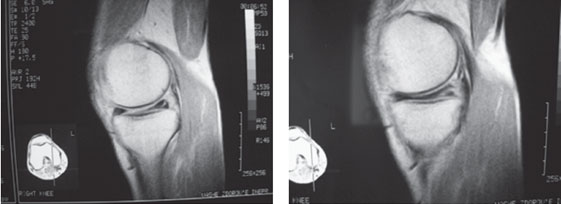

Для исключения повреждения костных структур проводят рентгеновские снимки. Разрывы мениска на снимках не видны, так как мениски прозрачны для рентгеновских лучей. Полностью установить диагноз помогают рентгеновские снимки с контрастированием сустава, ультразвуковое исследование, но более современными методами служат магниторезонансная томография или эндоскопическая артроскопия (осмотр внутренней поверхности сустава при помощи артроскопа).

uzi-diagnostika-УЗИ.jpg  mrt-diagnostika-МРТ.jpg

Полный разрыв заднего рога медиального мениска. УЗИ Полный разрыв заднего рога медиального мениска. МРТ